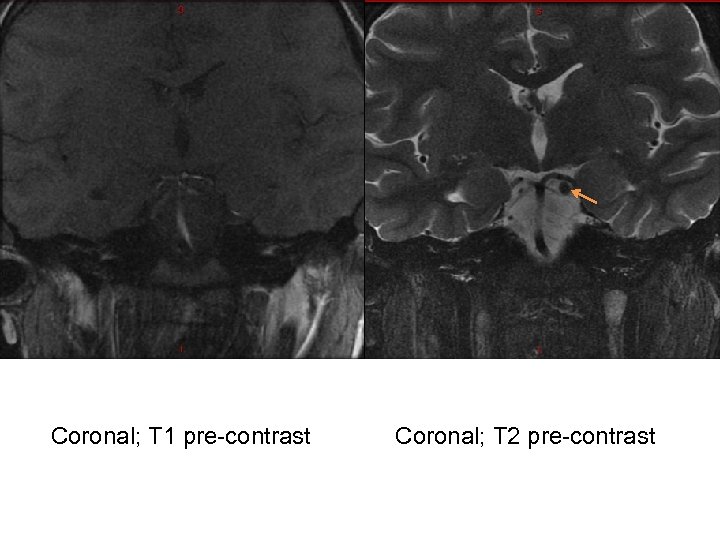

Our Patient – Diagnostic tests • MRI Brain – No obvious radiological abnormality • MRA Head and Neck – Normal • MRI Orbit (w/wo contrast): – At the left interpeduncular fossa between the left P 1 segment and superior cerebellar artery there is an enhancing 4 mm focal, round lesion involving the proximal left oculomotor nerve favored to represent a schwannoma. No connection to the vasculature seen.

Coronal; T 1 pre-contrast Coronal; T 2 pre-contrast